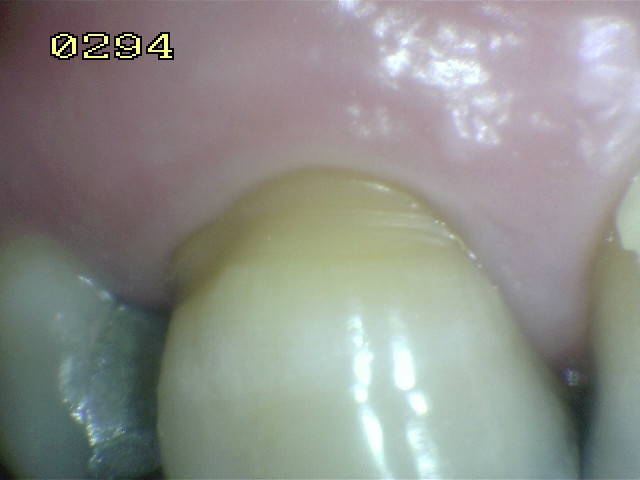

Código E:

Si la

superficie de la raíz

no puede ser visualizada

directamente como resultado

de la falta de la recesión

gingival,

entonces es

excluida. Ver imagen

inferior izquierda. Superficies

cubiertas completamente por

cálculos deben ser

removidos antes de

determinar el estado de

la superficie.